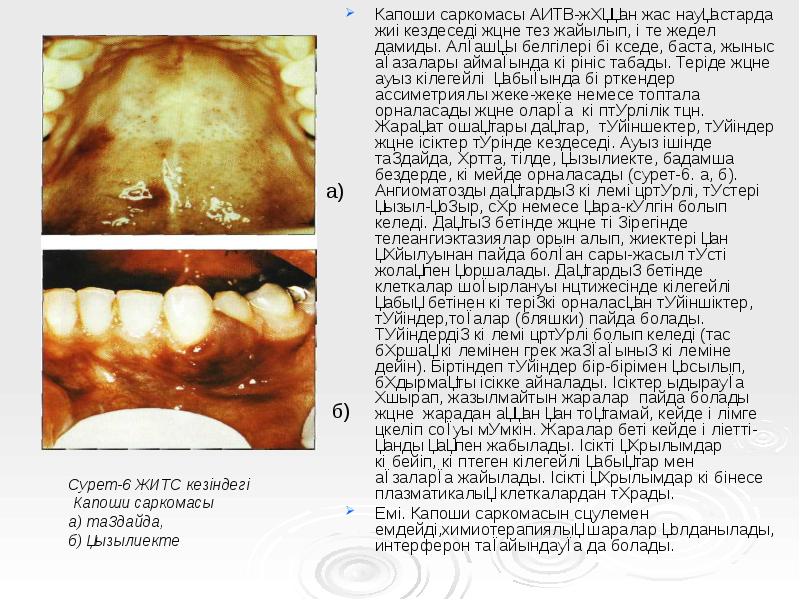

- 56. Капоши саркомасы АИТВ-жұққан жас науқастарда жиі кездеседі және тез жайылып, өте